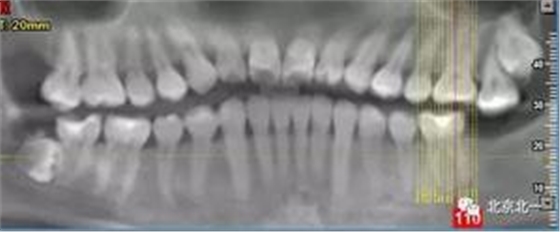

病例資料:一般情況,患者女性,28歲, 主訴:要求拔右側下頜智齒,檢查:右側下頜第三磨牙未見萌出, 拍片如圖。

圖一:CBCT顯示右側下頜水平骨埋伏牙,牙冠距離下牙槽神經管接近。

圖二:自帶的CBCT顯示下牙槽神經管貼著智齒走形。

圖三:截面圖顯示神經管位置。

總結:單純拍片看牙齒并不復雜, 通過微創拔牙有絲分裂可以避免傷及神經, 本病例特殊之處在于牙齒顏色和骨顏色無法區別。導致去骨或者分牙比較茫然, 不可大意,以及磨牙的手感和去骨的手感一致時,兩者不好區分。 只能偏向保守, 多角度拍片再三確認后予以安全拔除。 另外CBCT模式上看智齒位置也有誤差,醫師要根據經驗調整,特別是在這種哪里是骨,哪里是牙的情況,不能盲目大范圍去骨導致術中骨折。